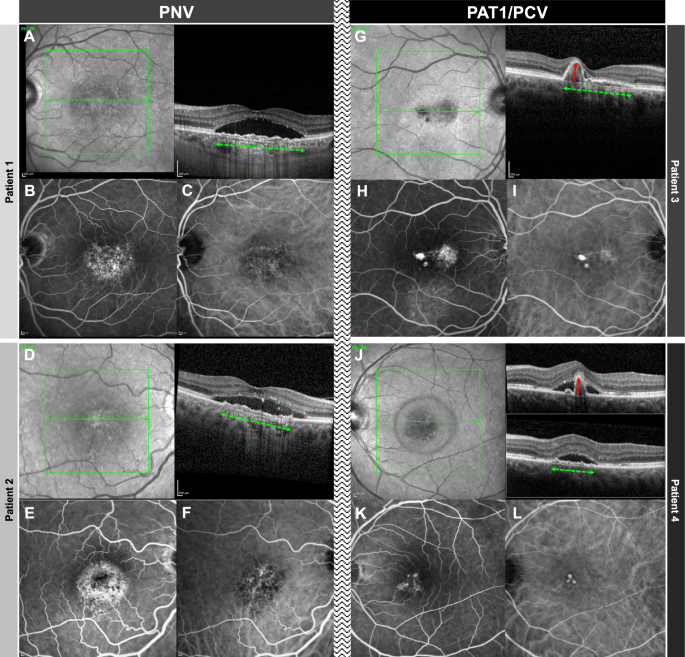

In patients 1 and 2 with PNV, OCT (A + D) demonstrates a flat irregular PED (alternatively double layer sign) and subretinal fluid. Note that the flat irregular PED has a wide horizontal diameter (green horizontal arrow) and low height. Whereas FA (B + E) shows unspecific hyperfluorescence, ICG (C + F) shows a type 1 choroidal neovascularization without evidence of aneurysmal/polypoidal lesions. In patients 3 and 4 with PAT1/PCV, OCT (G + J) shows a peaking PED (red vertical arrow) with greater height having an adjacent double layer sign (diameter demonstrated with a green horizontal arrow). FA (H + K) shows a more focal hyperfluorescence, and ICG (I + L) clearly demonstrates the presence of aneurysms/polyps.

SFCT and PED characteristics can be found in Table 1. SFCT was comparable between the PNV and the PAT1/PCV groups (377 ± 92 (185–589) vs. 400 ± 83 (272–505) µm; p = 0.39). Maximum PED diameter was also similar between the groups (1809 ± 645 (934–3301) vs. 2004 ± 613 (1196–2833) µm; p = 0.46). Maximum PED height was significantly higher in the PAT1/PCV as compared with the PNV groups (199 ± 31 (158–245) vs. 82 ± 46 (27–267) µm; p < 0.00001). These “PED peaks” occupied a mean 489 ± 149 (317–707) µm horizontal diameter, representing 25 ± 8 (19–42)% of the total PED diameter in PAT1/PCV eyes. Other than the “PED peak”, PED height was comparable between both groups (PNV: 64 ± 32 (23–149) vs. PAT1/PCV: 58 ± 14 (37–72) µm; p = 0.60). Whereas all (100%) eyes in the PAT1/PCV group exceeded 150 µm with their peaking PED, 39 out of 42 PNV eyes (92.9%) remained below 150 µm (Fig. 1).

A double layer sign was seen in all eyes in both groups (100%). A complex / multilobular PED was seen in all eyes (100%) with PAT1/PCV and in all eyes (100%) with PNV. A sub-retinal ring-like lesion was seen in 5 eyes (71.4%) with PAT1/PCV and in none of the eyes with PNV.